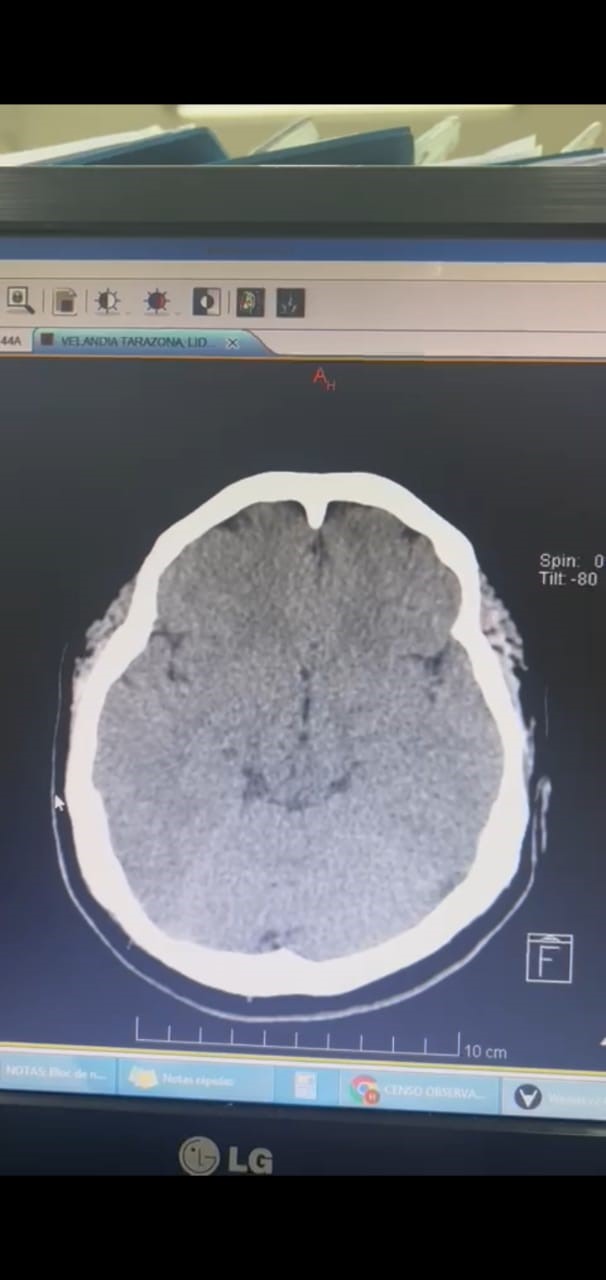

This is a 37-year-old female patient who presents after 11 days of vaccination with ChAdOx1-S agent against COVID-19 presents intense headache associated with symptoms of intracranial hypertension, after admission due to the aforementioned alarm symptoms and High blood pressure figures were initially taken to a simple cranial tomography showing the presence of cerebral edema and indirect signs of cerebral venous thrombosis.

Figure 1. Simple brain tomography performed on admission.